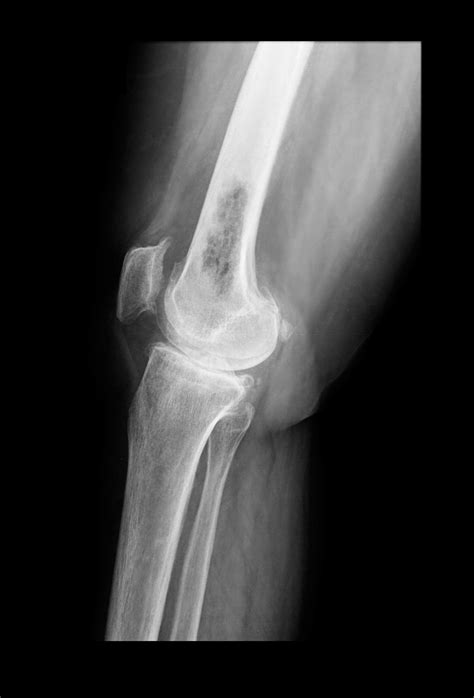

• Osteosarcoma: This is the most common type of primary bone cancer, typically affecting children and young adults. It often develops in the long bones of the arms and legs.

• Imaging Tests: X-rays, CT scans, MRI scans, and bone scans can help identify bone abnormalities and determine the extent of the cancer.